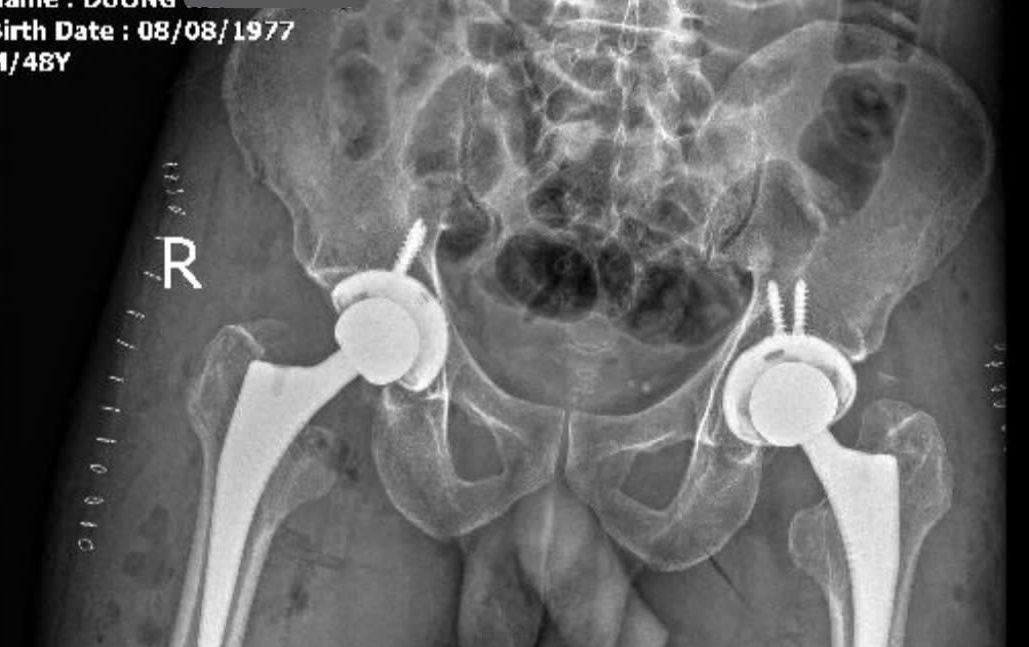

Hình ảnh chụp X-quang sau khi đã thay chỏm xương đùi 2 bên cho bệnh nhân

Ê kíp bác sĩ đã tiến hành phẫu thuật cho bệnh nhân qua đường mổ trực tiếp phía trước - phương pháp phẫu thuật ít xâm lấn trong thay khớp háng. Sau phẫu thuật, bệnh nhân phục hồi tốt và đến ngày thứ 2 đã có thể tập đi lại với khung hỗ trợ.